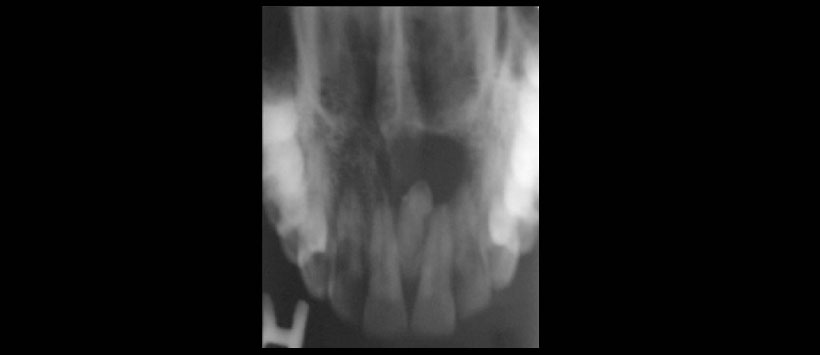

Figura 3: Radiografía oclusal superior que muestra la presencia de un diente supernumerario (mesiodens) en posición invertida con una imagen radiolucida pericoronal de limites definidos que se extiende de pieza 11 a pieza 22.